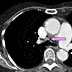

Axial contrast-enhanced chest CT shows mild precarinal lymphadenopathy (purple arrow).

Axial contrast-enhanced chest CT at a lower level shows thickened interatrial septum of largely fat attenuation (blue arrow) and rather prominent epicardial fat (green arrow).